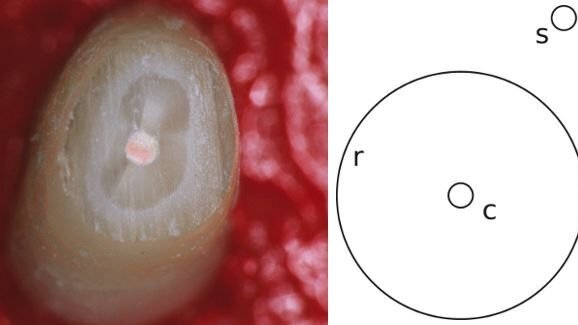

Dans les essais cliniques de huit praticiens néo-zélandais, spécialisés en endodontie, réalisés en 2002 et 2006, les chercheurs ont constaté que les chirurgiens-dentistes ont tendance à tomber dans le piège de l'illusion optique de Delbœuf, qui fait que les espaces clos apparaissent plus petits qu'ils ne le sont en réalité, dans un contexte plus large. Dans ces essais, une cavité dans une dent semblait être plus petite lorsque les tissus environnants se situaient dans la fourchette des paramètres de l'illusion, conduisant à retirer plus de tissu sain que n’était nécessaire.

Lors de l'étude, plus de 20 dents extraites avec racines obturées ont été traitées par chaque participant, qui n’avaient pas été informés sur les paramètres de l'illusion. Les participants étaient invités à supprimer le moins de tissu possible lors de la préparation des dents, et à utiliser leurs instruments à main de façon habituelle.